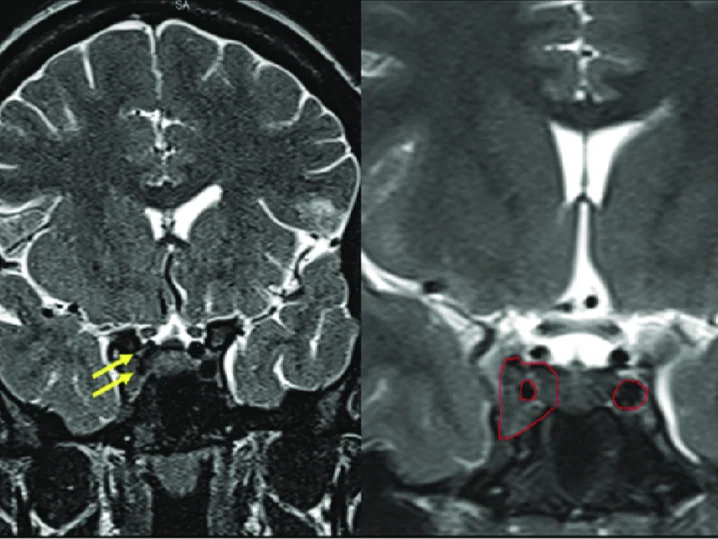

La resonancia magnética de silla turca o hipófisis es una técnica de imagenología que permite evaluar detalladamente la glándula hipofisaria o pituitaria.

Es una técnica de imagen avanzada que evalúa la denominada “silla turca”, una estructura ósea ubicada en la base del cráneo, en el hueso esfenoides. La silla turca alberga la glándula pituitaria o hipófisis que es fundamental para la regulación de diversas funciones hormonales en el cuerpo.

Este procedimiento utiliza un campo magnético fuerte, ondas de radio y tecnología computarizada para obtener imágenes detalladas de la glándula pituitaria y sus regiones anatómicas vecinas, tales como los senos cavernosos y la cisterna supraselar.